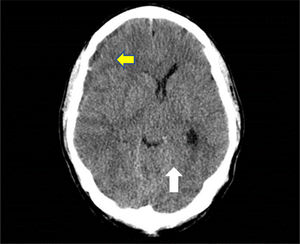

A skull CT scan was performed and revealed a hypodense collection with hyperdense areas at the right parietal subdural level. This was compatible with chronic subdural hematoma with rebleeding areas and large mass effect with ipsilateral ventricular compression and 9mm midline deviation (Fig. 1). With these findings and neurosurgical assessment, treatment started with intravenous dexamethasone 40mg daily was iniciated.